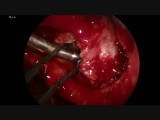

Surgery - Nasal Tumors

in Dogs - Sinus